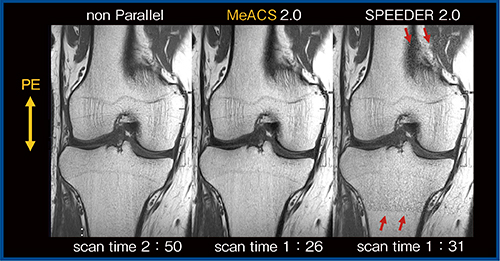

図4は,parallel imagingなし,MeACS,SPEEDER(SENSE)の画像比較であるが,MeACSではエンコード方向の依存性が低く,展開エラーもまったく見られない。MeACSは,compressed sensing単独,CS→PI,PI→CSという従来法の問題点を解決できると考えている。

図4 エンコード方向の依存性の比較(W.I.P.)